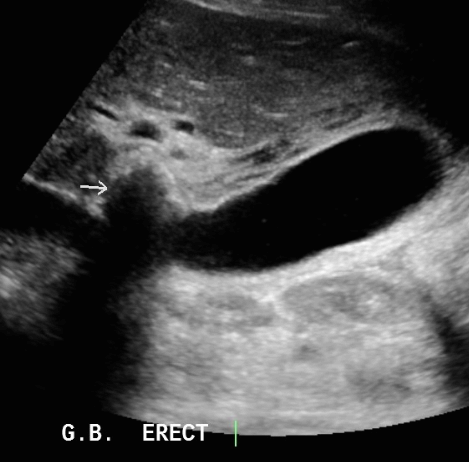

급성담낭염 US finding

- 담낭관내 결석

- 담낭벽이 두꺼워진다 ( GB wall thickness 3mm 이상)

- GB내강의 압력증가 및 확장 (width 5cm 이상)

- color doppler 시 GB wall 혈류증가 GB lumen bile sludge (내부에코증가)

- 급성담낭염은 담낭주위 액체저류 (pericholecystic fluid)

- 심한 RUQ pain (Murphy sign) : 젊은 환자에서는 대부분 Murphy sign이 있지만, 노인에서는 Murphy sign이 없더라도 급성 담낭염이 있는 경우가 많으므로 더 주의 깊게 관찰해야 한다.